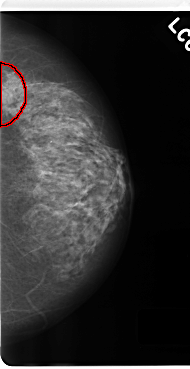

C_0228_1.LEFT_MLO

C_0228_1.LEFT_CC

FILE: C_0228_1.LEFT_CC.OVERLAY

TOTAL_ABNORMALITIES 1

ABNORMALITY 1

LESION_TYPE MASS SHAPE ROUND MARGINS CIRCUMSCRIBED

ASSESSMENT 4

SUBTLETY 5

PATHOLOGY MALIGNANT

TOTAL_OUTLINES 1

BOUNDARY